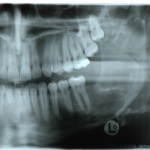

Previsione d’inclusione dei terzi molari e indicazioni alla loro estrazione